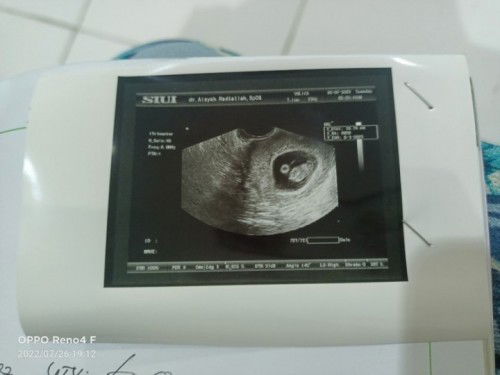

Assalamualaikum bunda", mau tanya sebelumnya. Hari ini pertama kali aku ke dr. obgyn, kalau di hitung dri hpht tepat hari ini usia kandungan ku 7 minggu. Tapi waktu di usg kantong janinnya juga blum terlihat, apakah ini normal atau disini ada yg pernah mengalami hal serupa? Aku d kasih obat penguat janin sama folamil genio ##seriusnanya #bantusharing #ingintahu #pleasehelp